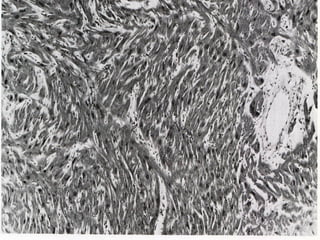

• #31 This is a microscopic view of the myocardium seen under 160 x magnification that shows groups of myocardial fibers that are arrange haphazardly as well as replacement of some myocardial fibres by connective tissue.

• #32 This is a microscopic section of the myocardium showing a cross-section of a small branch of the coronary arteries seen under 160 x magnification. The artery is seen to have thick walls and reduced luminal cross-sectional area. Presumably the arterial wall changes are secondary to the myocardial disease.

• #33 This is a microscopic view of a cut section of the heart seen at 160 x magnification. This shows the bizarre arrangement of clusters of myocardial fibers as seen in hypertrophic cardiomyopathy. This section is from a 7 year old girl who died suddenly and unexpectedly.